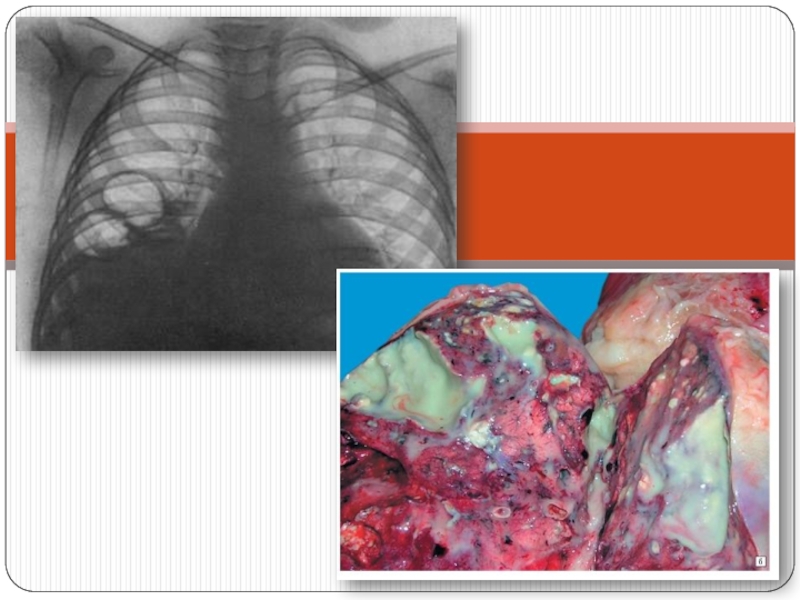

Слайд 29Өкпе гангренасы дегеніміз не?

Өкпе тінінің массивті инфильтрациясы фонында некроз

болады, ал сау және зақымданған тін арасындағы демаркациялық шекара мүлдем

болмайды. Жиі өкпенің төменгі бөлігі зақымдалады. Ол өкпені зақымдалуымен қатар бүкіл ағзаны зақымдайды.

Өкпе гангренасы дегеніміз не? Өкпе тінінің массивті инфильтрациясы фонында некроз болады, ал сау және зақымданған тін арасындағы

Слайд 34Диагностикасы

Физикалық зерттегенде зақымдану аймағы перкуссияда дұрыс емес контурлы ошақ түрінде

анықталады. Перкуторлы дыбыс тұйық, дауыс дірілі күшейген.

Аускультацияда әртүрлі калибрлі

көптеген ылғалды сырылдар естіледі.

Рентгенологиялық зерттегенде өкпенің сәйкес зонасында шекаралары анық емес, күн сайын прогрессивті өсетін бірыңғай қараю аймағын көруге болады. Плевралық қабаттасу байқалады.

ДиагностикасыФизикалық зерттегенде зақымдану аймағы перкуссияда дұрыс емес контурлы ошақ түрінде анықталады. Перкуторлы дыбыс тұйық, дауыс дірілі күшейген.